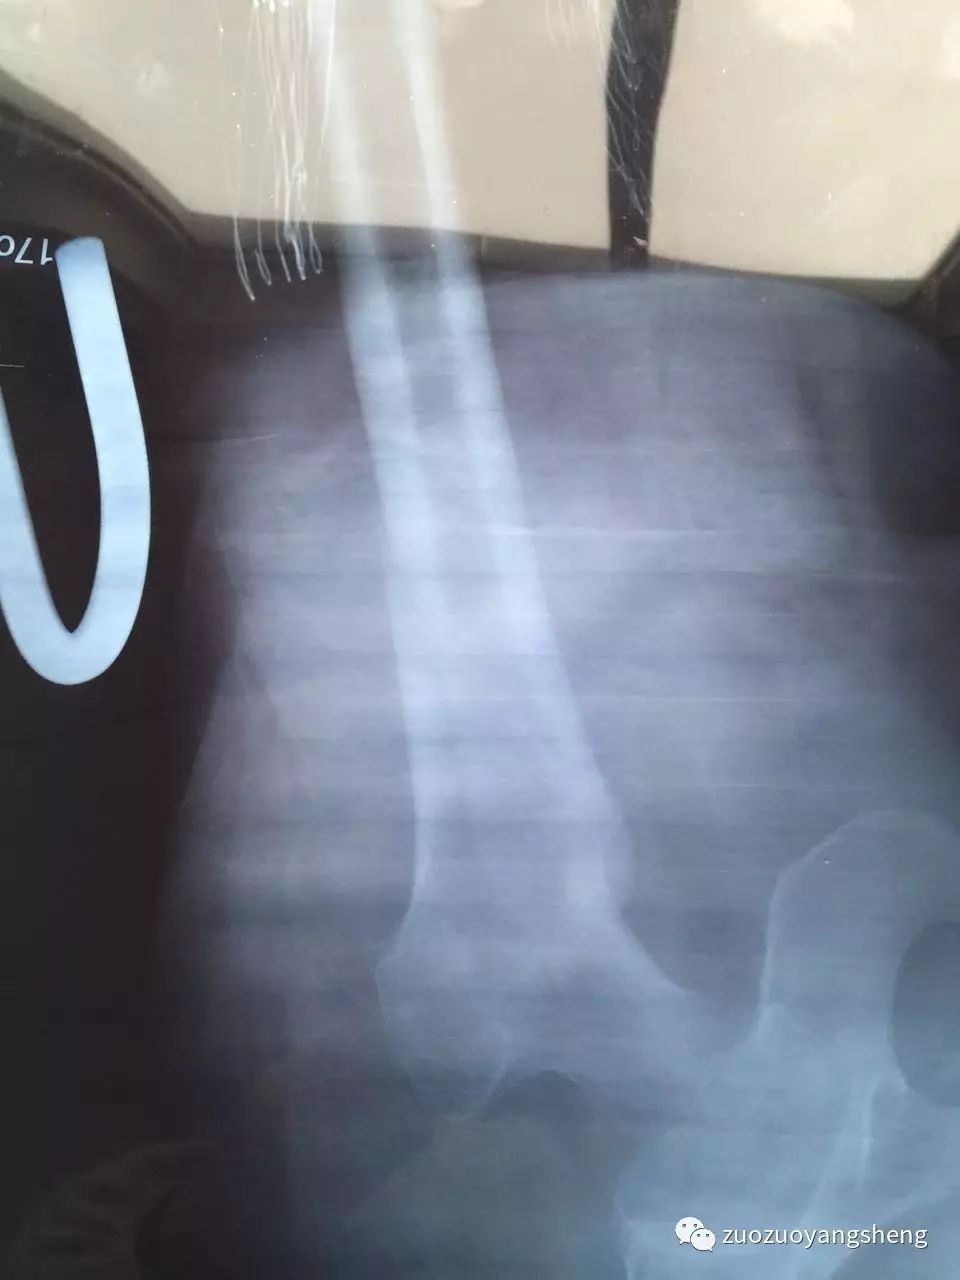

大家好,我是左左。在我收到方老师发过来的案例时,比较震惊,80几岁的婆婆能在短短几周里迅速愈合,确实有点不可思议。婆婆在某三甲医院的时候,医生是建议手术,而且必须手术。当家人选择保守治疗,选择使用原始点,才发现保守治疗的效果比手术治疗的效果更好,伤害更少,费用更低。

收到案例后的当天晚上,我就在想,自己母亲的粉碎性骨折是否也可以手法复位,保守治疗呢?然后开始陷入深深的自责中。去年母亲髌骨粉碎性骨折后,医院强烈建议手术治疗,说保守治疗可能需要在床上躺6个月,而且不能随意挪动。所以自己当时考虑到母亲不能动,长时间不能动,不能下床,更不能运动,这样下去怕影响整个身体,后决定采用医生建议,进行手术治疗。现一路走来,手术治疗这个方案,不到万不得已,原始点家人们尽量不要使用。手术前需要打针消炎(寒凉药物),手术中需要切割皮肤、肌肉等各身体组织,需要打麻药(超级寒凉药物),需要打钢钉固定骨头,手术后同样需要7天输液消炎(寒凉药物)……半年后还需要手术取出钢钉,还需要消炎(还好当时医院床位紧张,所以没有消炎,让回家自行打针消炎,我强烈反对,所以没打。)经过这样伤害性的治疗方法,虽然有给母亲使用原始点,按推、温敷和喝姜汤,但母亲的脚还是没能完全恢复。骨折至今已经8个月了,走路依然是一瘸一拐,膝关节里面还经常感觉紧绷,经常感觉疼痛。

如今,跟方老师提供的案例进行对比,骨折后选择手术治疗方案真的不是最佳治疗方案,遇到类似情况,特别是年轻人、小朋友,如果在遇到骨折后,选择保守治疗方案,配合使用原始点,因为身体热能足,也许修复起来更快更好。